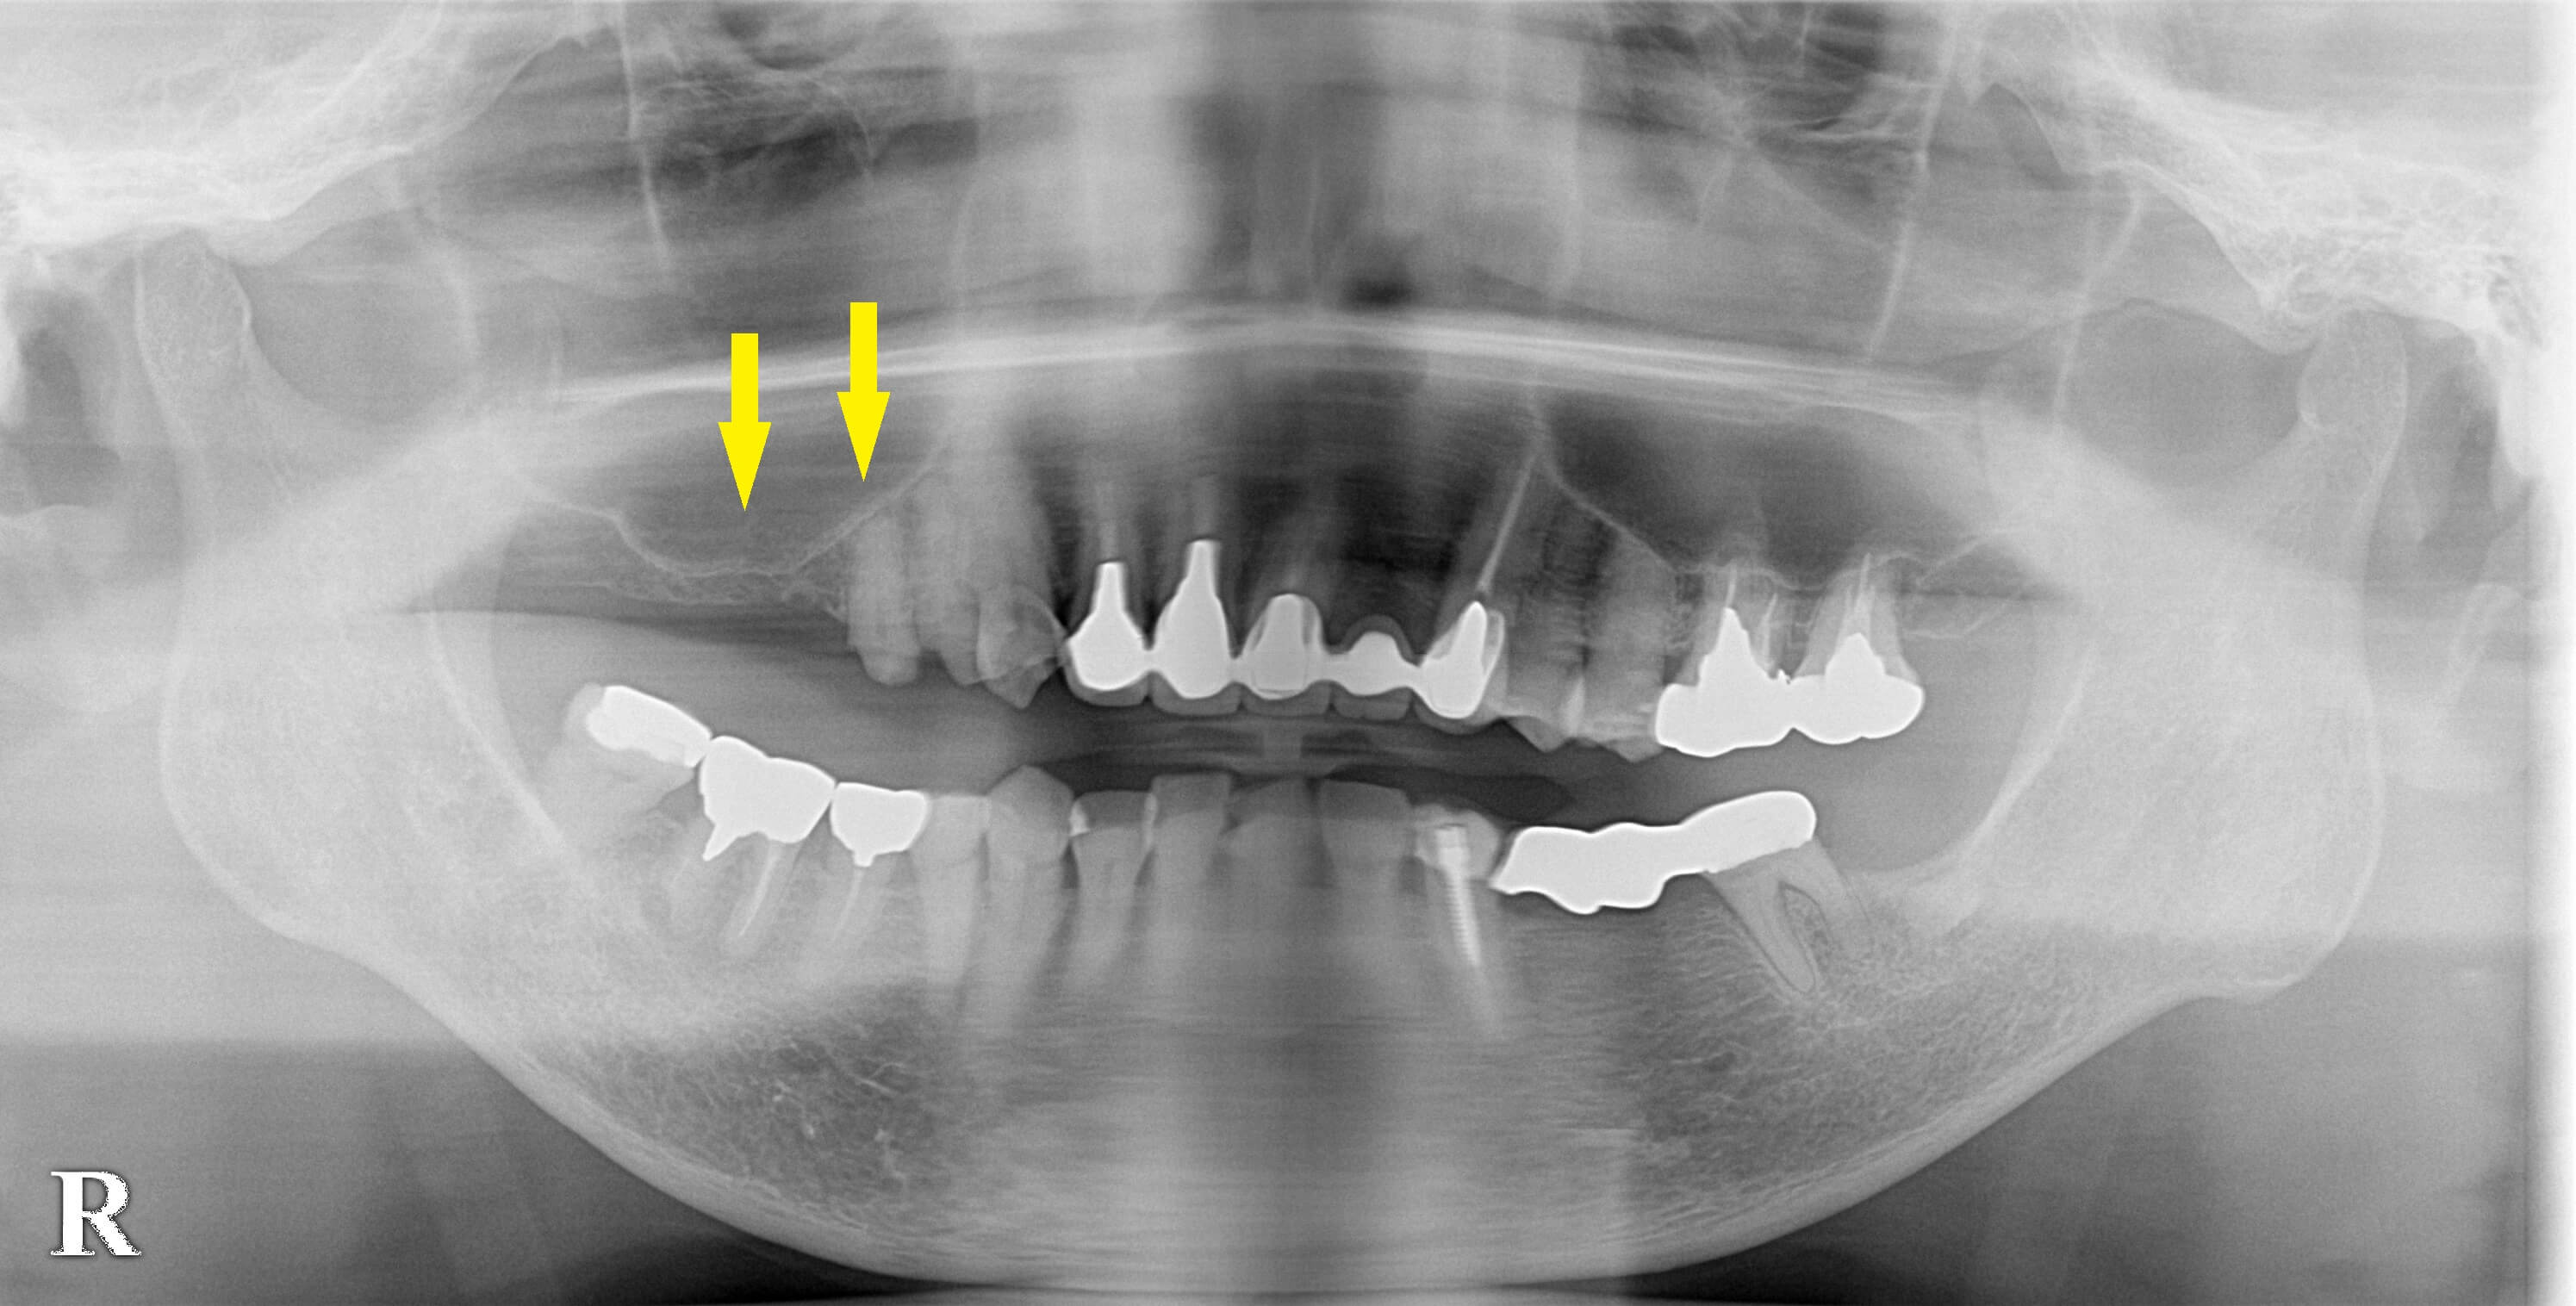

右上顎第二小臼歯が破折しているといわれ、右上顎臼歯のインプラント治療を希望されて来院されました。

右上顎第二小臼歯の差し歯が、歯根破折のため外れていました。

その後方の歯がない部位もインプラントを入れたいとのことでした。

レントゲン、CTを撮影してみると、後方の第一大臼歯部は、骨が非常に薄く、通常のインプラント埋入はできませんでした(下の写真2段目左右が手術前のCT)。

そこで、まずサイナスリフトという骨造成術で、大きく骨を増やし骨ができたら、第一大臼歯部のインプラント埋入と同時に、第二小臼歯の抜歯即時埋入を行う計画としました。

サイナスリフト後6か月が経過し、下の写真3段目左右のように、CTにて、骨造成がうまくいっていることが確認できましたので、本日、第一大臼歯部のインプラント埋入と同時に第二小臼歯の抜歯即時埋入を施行しました。